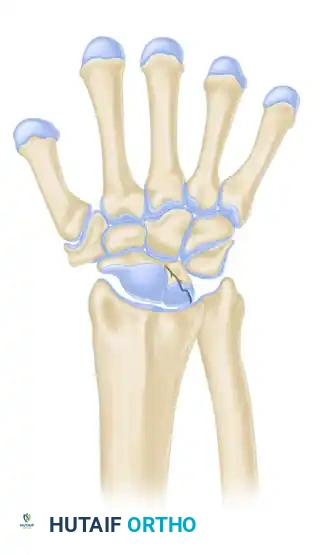

Stage IIIB

- Description: Lunate fragmentation is accompanied by fixed rotation of the scaphoid (dorsal intercalated segmental instability - DISI pattern) and proximal migration of the capitate.

- Treatment: Proximal row carpectomy (PRC) or STT fusion. The internal collapse pattern must be addressed.